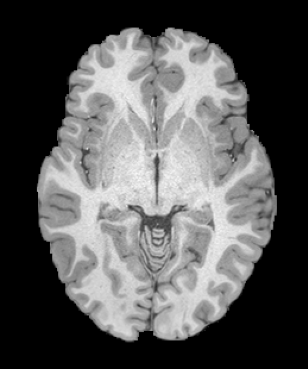

HCP Brain MRI We train on 1076 brain-extracted T1w images from the HCP dataset [24] and test on a sample of 100 pairs between 36 images via mean Dice over 28 midbrain structures [20, 21]. We train and execute the network at [130155130], then compute the Dice score at full resolution.

OASIS Brain MRI We use the OASIS-1 [12] data preprocessed by [9]. This dataset contains images of 414 subjects. Following the data split in [14], we train on 255 images and test on 153 images555Due to changes in the OASIS-1 data, our test set slightly differs from [14]. We evaluate all methods using our testing protocol so that results are consistent.The images in the dataset are of size [160192224], and we crop the center of the image according to the preprocessing in [14], leading to a size of [160144192]. During training, we sample image pairs randomly from the train set. For evaluation, we randomly pick 5 cases as the fixed images and register all the remaining 148 cases to the 5 cases, resulting in 740 image pairs overall.

| Moving Image | Warped Image | Fixed Image | Moving Image | Warped Image | Fixed Image |